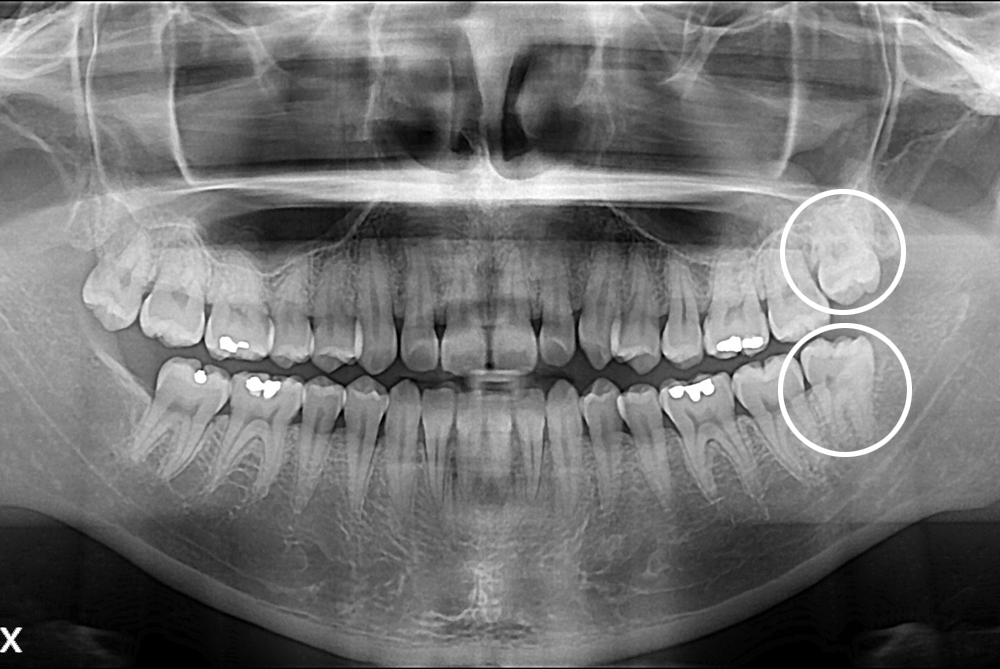

[사랑니] 난발치 사랑니 발치

치료후 : 2017-04-27

세종치과는 구강악안면외과학 박사이신 원장님이 발치하는 치과입니다.